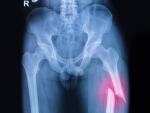

A broken leg can take you out of your activities for weeks to months. Recovery from a broken or fractured leg depends on the type, location, and complexity of the fracture. For example, a fractured thighbone (femur) generally takes more time and complex treatment than a broken fibula in the lower leg. Read on to learn more about broken legs and tips to make your recovery as smooth as possible.

Some simple leg fractures allow you to move around right away. Complex and thighbone (femur) fractures may require a period of traction and bed rest, or surgery. In either case, you’ll add activities and intensity slowly. Follow your doctor’s instructions. Doing too much can cause problems, such as movement of the broken bone. If your leg starts to hurt or swell, it’s time to rest it. Ask your doctor when it is safe to return to daily activities, work, and other activities.